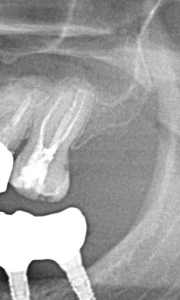

Furcațiile (ramificațiile) din profunzimea canalelor reprezintă o complexitate anatomică ce poate influența designul cavității de acces, în special la dinți precum premolarii mandibulari.

Prin utilizarea microscopului dentar operator, medicul poate realiza o cavitate de acces cât mai mică posibil, care permite un control superior al procedurii și păstrarea unei cantități maxime de structură dentară sănătoasă. Astfel, tratamentul endodontic atinge un echilibru optim între eficiența mecanică și respectarea principiilor biologice, pentru rezultate predictibile și durabile.